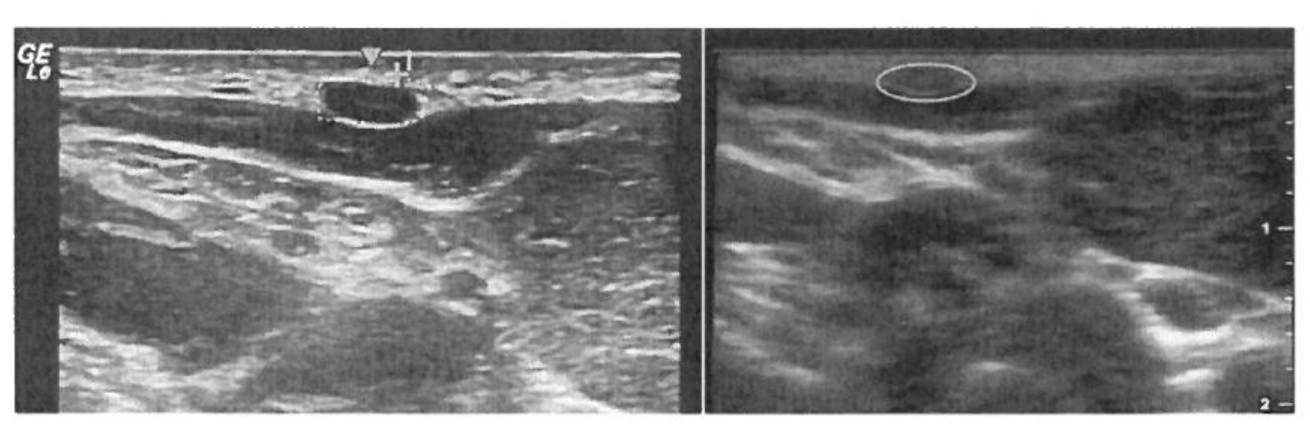

Fig 2. These images are of the left greater auricular nerve. The image with GE in the upper left corner is from the standard ultrasound device, and the other image is from the hand-held ultrasound device. The nerve is circled in both images, and it measured 9 mm2.

Eight individuals with leprosy were studied. Their demographics are included in Table 1. The mean cross-sectional area values are reported in Table 2. Based on reference values,[5-7] the nerves with the greatest enlargement were the ulnar 4 cm proximal to the elbow (230% of normal), the ulnar at the midhumerus (160% of normal), and the greater auricular nerve (390% of normal). Using all sites in all individuals, the Pearson product-moment correlation was .76 (P< .001) between the cross-sectional areas measured with the standard and the handheld ultrasound devices (Fig 1), and correlations for individual sites are included in Table 2. When only the three nerves with the greatest enlargement were assessed, the Pearson product-moment correlation was .73 (P< .001) between the two devices. Figure 2 shows a representative nerve image with each device.